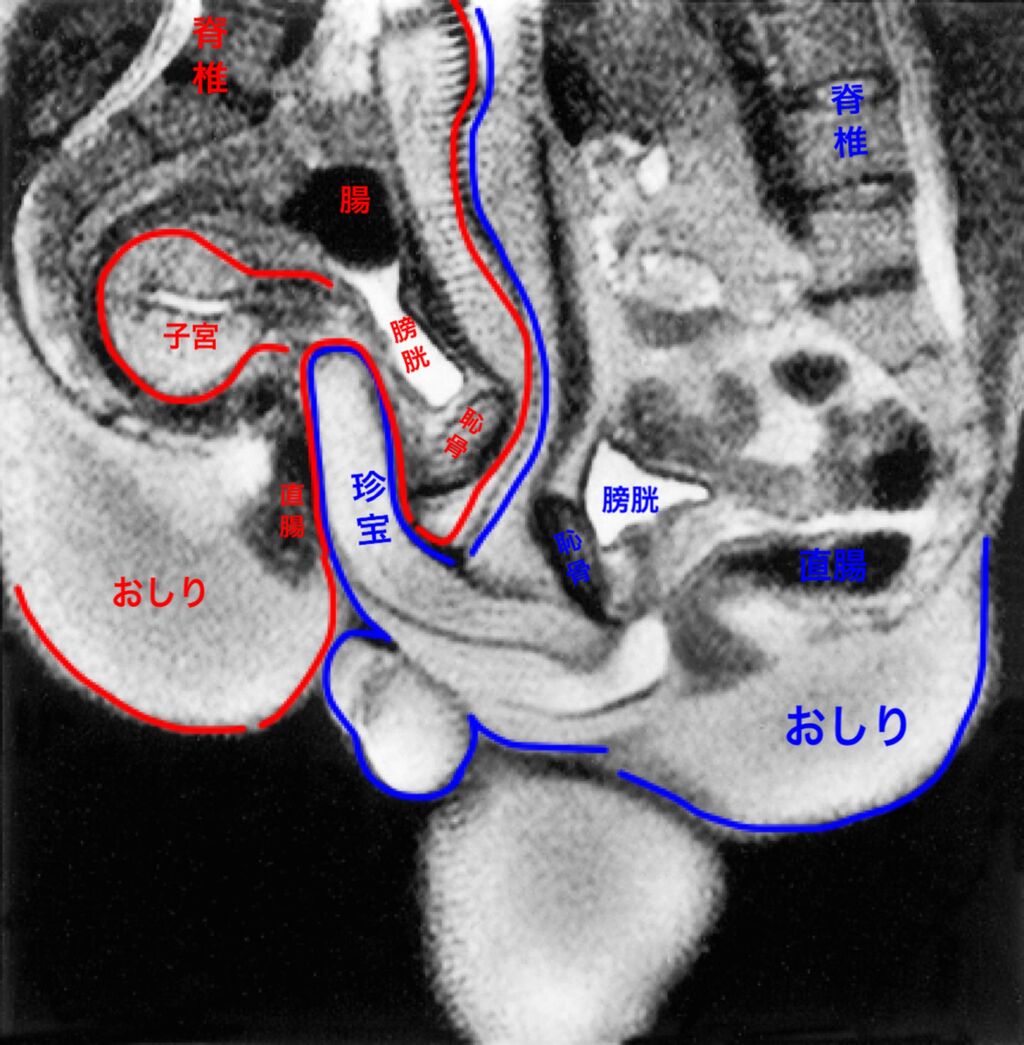

なんでこの形なんだろうね

生殖器官

スレ画の構造だとそうじゃないなら受精できないからな

>リアルのセックス中の断面図なんてあるんかな?

fu6552586.jpg

子宮が背中側に曲がってるか腹側に曲がってるかは個人差みたいな話もあったと思う

人間が直立だから急に曲がって変に思えるけど四足歩行の動物で考えると子宮が吊られる位置になって丁度いいんだろうな

>人間が直立だから急に曲がって変に思えるけど四足歩行の動物で考えると子宮が吊られる位置になって丁度いいんだろうな

すごく納得した

子宮口突くのいてぇからやめろ!!子宮口の前後は気持ちいいからどんどん突いていいよ♥みたいなのどこかで見たけどこれかあ

なんか分かれ道のハズレの方の行き止まりにちゃんと宝箱置いてあるタイプのダンジョンみたいだね